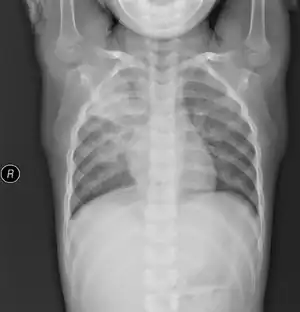

![]() ![]() | |